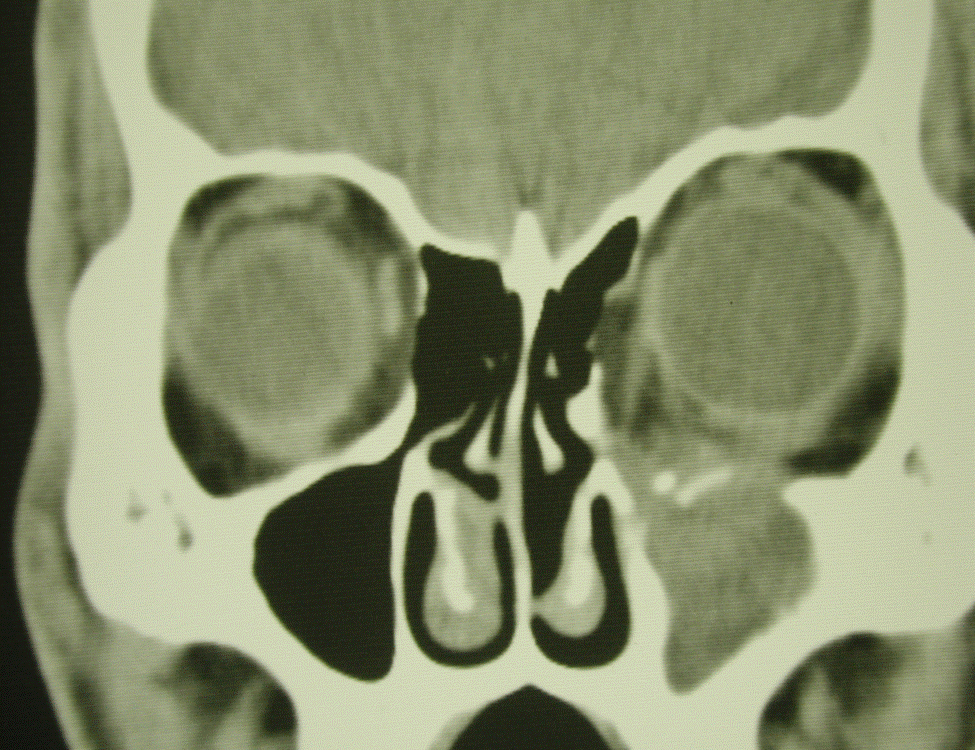

- Figure 6. CT scan of orbits showing blow-out fracture of orbital floor